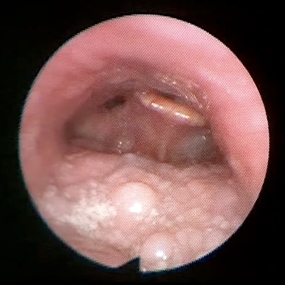

Bei Patienten mit einem habituellen Schnarchen oder mit einem Schlafapnoe-Syndrom, welche die cPAP-Maskenversorgung nicht wünschen oder nicht vertragen, kann geklärt werden, wo genau das Schnarchen entsteht. Dieses erfolgt durch eine Endoskopie im künstlichen Schlaf (Propofol-Somnoendoskopie), welche ambulant im Krankenhaus durchgeführt wird. Man geht dabei mit einem dünnen flexiblen Endoskop (Nasopharyngoskop) über die Nase in den Nasenrachen. Der Patient bekommt dann das Narkosemittel Propofol, womit ein künstlicher Schlaf eingeleitet wird. Im Regelfall fängt der Patient an zu schnarchen und man kann über das Endoskop beobachten welcher Mechanismus für das Schnarchen ursächlich ist. Bei der Endoskopie wird auch durch den Anästhesisten ein Esmarch-Handgriff durchgeführt. Dieser Handgriff (bekannt aus dem Erste-Hilfe-Kurs) bewirkt eine Vorverlagerung des Unterkiefers. Der endoskopierende HNO-Arzt sieht dann welchen Effekt dieser Handgriff auf die Engstellen und die Geräuschentstehung des Schnarchens hat. Somit kann der Erfolg einer Protrusionsschiene (eine der Therapieoptionen) abgeschätzt werden. Die Propofol-Somnoendoskopie ist ungefährlich und nicht schmerzhaft. Falls sie doch als unangenehm empfunden wird, kann die Nase auch lokal betäubt werden.

Meistens entsteht das Schnarchen durch Vibrationen im Bereich des Gaumensegels inklusive der Uvula (Zäpfchen) oder des Rachens (siehe Video). Aber auch Vibrationen im Bereich der Epiglottis (Kehldeckel) mit Ansaugphänomen oder im Bereich des zurückfallenden Zungengrundes werden beobachtet.

epiglottische Rhonchopathie bei "floppy epiglottis" mit Vibrationen und Schnarchgeräuschentstehung (leider ohne Ton) links vom Kehldeckel

Bitte auf das Bild klicken, um das Video zu laden. |